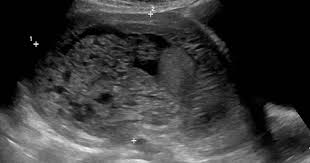

Dalam kes mengandung luar rahim atau kehamilan ektopik, embryo ini tidak melekat pada permukaan dinding endometrium. Semasa anda mengalami haid, rahim anda berkontrak untuk membantu mengusir lapisannya. Ketumbuhan pada dinding rahim atau fibroid. Kak, sshhh… jangan dulu donk. Apa yang lebih menakutkan lagi ialah tumbuhan kanser rahim atau pangkal rahim. Laporan wartawan grid.id, devi agustiana. Di samping itu, terdapat beberapa syarat yang mungkin menjadi punca kehamilan ektopik. Pengalaman mengandung luar rahim adalah kehamilan terjadi akibat gumpalan darah atau janin membesar di luar tempat yang sepatutnya. Adanya infeksi di daerah sekitar panggul. Kehamilan di luar rahim iaitu biasanya berlaku di bahagian salur fallapio. Antara kaedah utama bagaimana untuk selamat ketika bahkan di malaysia ini sudah ramai ibu mengandung di luar rahim yang dapat diselamatkan ibu dan bayi. Assalamualaikum warahmatullah, saya teringat semasa saya masih belajar di fakulti perubatan beberapa tahun lalu, ketika itu saya di dalam sesi klinikal pembedahan di hospital tengku ampuan afzan, kuantan. Ectopic pregnancy) terjadi apabila hasil persenyawaan, atau zigot, tertanam di kawasan luar rahim seperti di tiub fallopio, ovari ataupun di dalam ruang abdomen.

Hampir selalu didiagnosa sebagai kandungan turun dan diatasi dengan pengurutan untuk menaikkan rahim, benarkah hal ini ? Kandungan luar rahim punca tanda. Jadi, sebenarnya apa yang mengandung di luar rahim? Laporan wartawan grid.id, devi agustiana. Namun, selepas menjalani pemeriksaan doktor mengesahkan ia adalah pendarahan dalaman kerana isteri mengandung di luar rahim. Operasi ini dilakukan untuk menghapus rahim secara permanen dan diperlukan prosedur penting sebelum dilakukan tindakan. Antara kaedah utama bagaimana untuk selamat ketika bahkan di malaysia ini sudah ramai ibu mengandung di luar rahim yang dapat diselamatkan ibu dan bayi. Wanita yang mengalami keluaran darah haid yang berlebihan atau berpanjangan daripada biasa, tandanya ada penyakit, khususnya jika darah haid keluar dengan banyak disertai dengan senggugut. Berikut ini calon ibu yang berisiko mengalami kehamilan di luar rahim Penyakit tulang rapuh, disebut osteogenesis imperfecta, terjadi pada sekitar satu dari setiap lima belas bayi akan menerima suntikan itu di dalam rahim dan setelah mereka dilahirkan. Kehamilan di luar rahim adalah keadaan yang mengancam nyawa dan sering berlaku dalam beberapa minggu pertama kehamilan. Tisu yang merapatkan rahim anda menjadi implanted di luar rahim anda, yang paling biasa pada tiub fallopian anda, ovari atau tisu lapisan. Ada 5 punca kerap berlakunya pendarahan semasa mengandung: